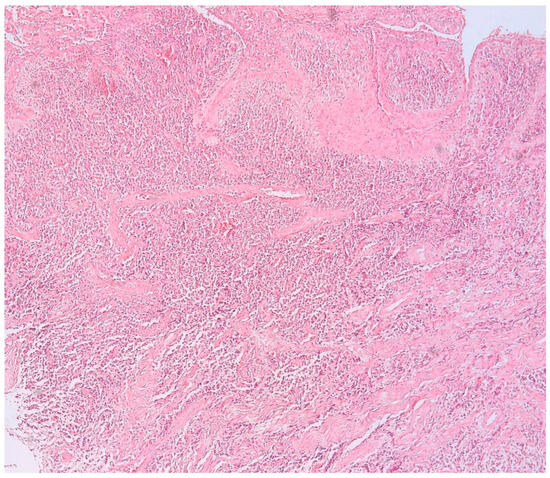

3.1. Morphologic Analysis

3.2. Mast Cells

3.3. Aspects of Microvessels